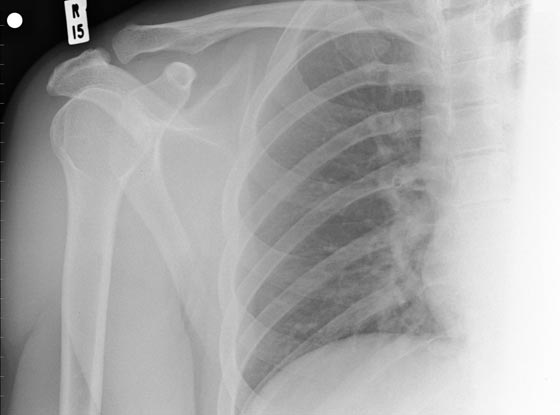

مع التقدم في العمر، تبدأ أمراض هشاشة العظام في الظهور بشكلٍ كبير. توصَّل الباحثون إلى وجود جين يُدعى "LRP5"، مسؤول عن تنظيم كثافة وثبات سُمك العظام، وكشفوا أيضاً عن تسبب حدوث طفرة في هذا الجين، في ضعف وهشاشة العظام. مع هذا، يُمكن أن يُحدث نوع مختلف من الطفرات في الجين نفسه تأثيراً معاكساً، يؤدي إلى تمتع أصحابها بعِظام كثيفة وقوية، لا تنكسر حتى عند التعرض للحوادث.

لاحظ هذا الأمر للمرة الأولى الدكتور "كارل إنسوغنا Karl Insogna" بجامعة "ييل"، في 20 شخصاً من أفراد عائلة واحدة، يملكون كثافة عظمية هائلة. بحث بعدها "إنسوغنا" عن السبب ليجد طفرة في جين "LRP5" وراء الأمر، ويطمح العلماء إلى استغلال هذه الطفرة في التوصل إلى علاج فعّال لهشاشة العظام.